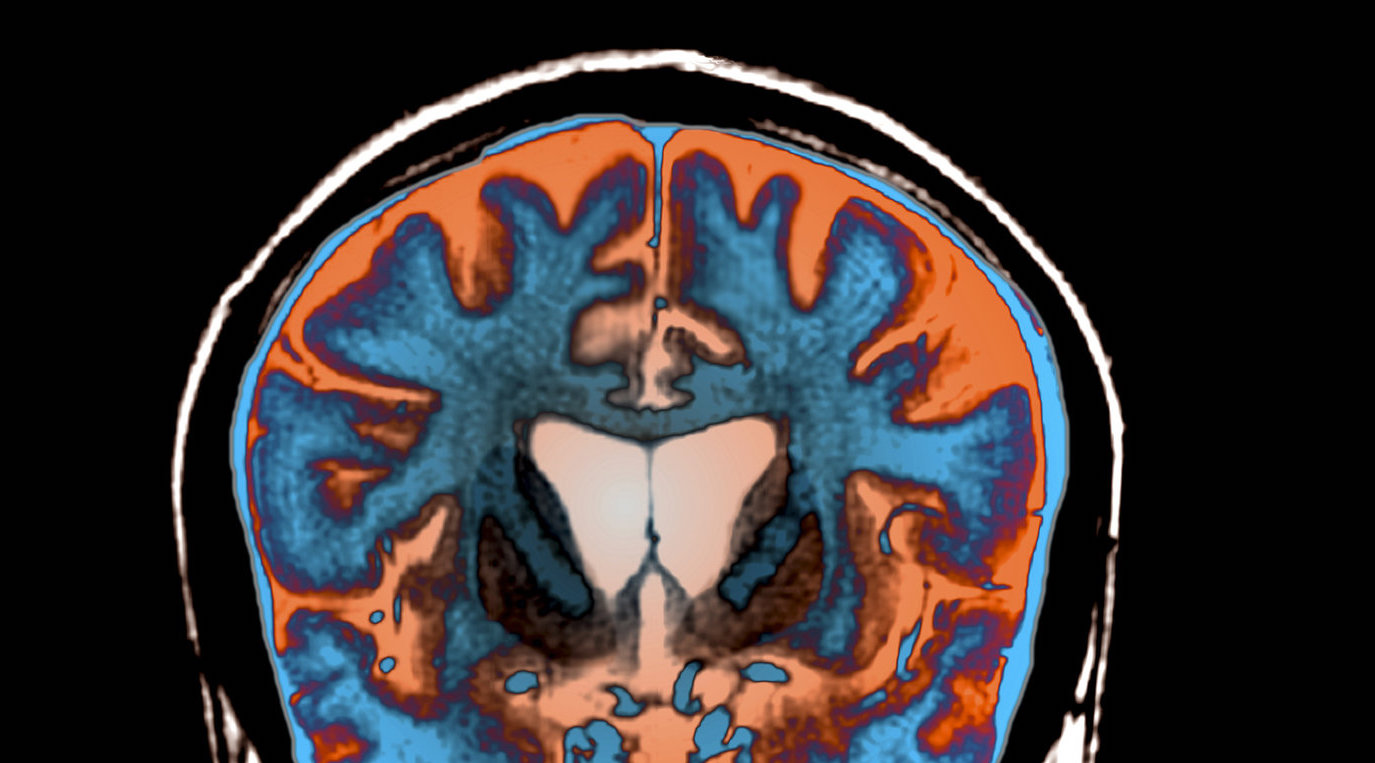

An MRI scan shows signs of atrophy in the brain of a patient with Huntington's disease.

Science Photo Library/Science Source